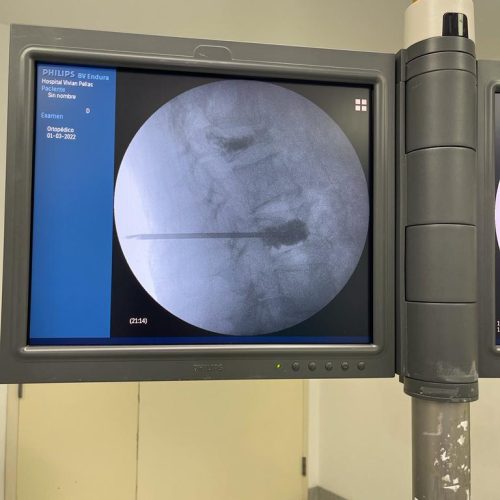

Rizólisis (Ablación por Radiofrecuencia)

Técnica mínimamente invasiva para tratar el dolor crónico articular de la columna

¿Qué es?

La rizólisis es un procedimiento no quirúrgico que utiliza energía de radiofrecuencia para inactivar de forma selectiva los nervios responsables de transmitir dolor desde las articulaciones facetarias de la columna.

¿Para quién está indicada?

- Pacientes con dolor lumbar o cervical crónico, de origen mecánico

- Artrosis o degeneración de las articulaciones facetarias

- Dolor que no responde a tratamiento conservador (analgésicos, fisioterapia, bloqueos)

- Personas que no son candidatas a cirugía mayor